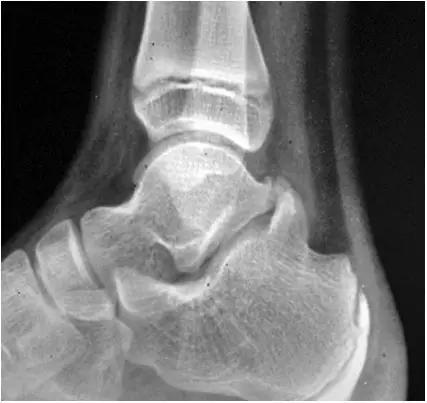

男,11岁,自述后踝下方疼痛,活动时为甚,并有一突起。

- 踝关节正侧位X 线平片,侧位片均显示距骨后方有三角形或椭圆形的距后三角骨。部分病例伴有轻度的踝关节骨性关节病。

- MRI 检查示距后三角骨及周围软组织有水肿信号,距后三角骨和距骨之间正常的低信号纤维连接中断,出现液性信号。